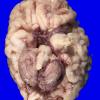

Menkes disease (4)